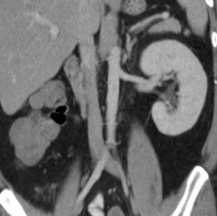

КТ, корональная реформация. Агенезия правой почки.